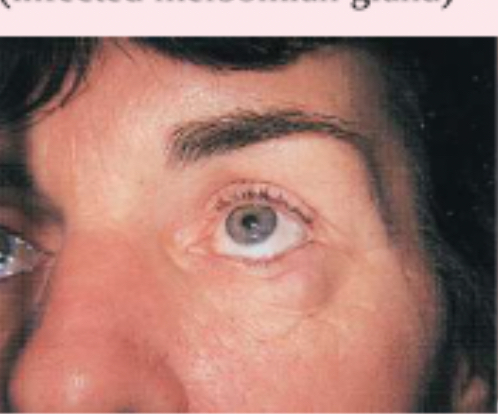

chalazion

infected meibomian gland